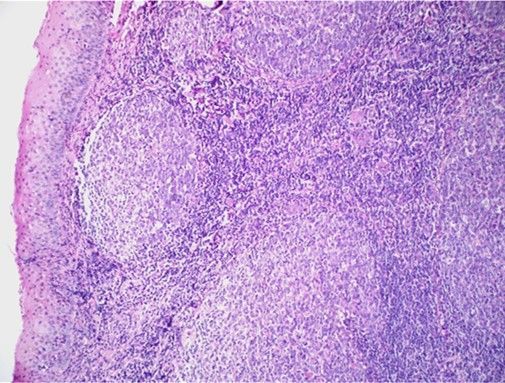

Question 8

Question

Label this image

Image:

88ba1779-3d70-4e37-86b3-21b2ff592954 (image/jpeg)

Answer

Spleen